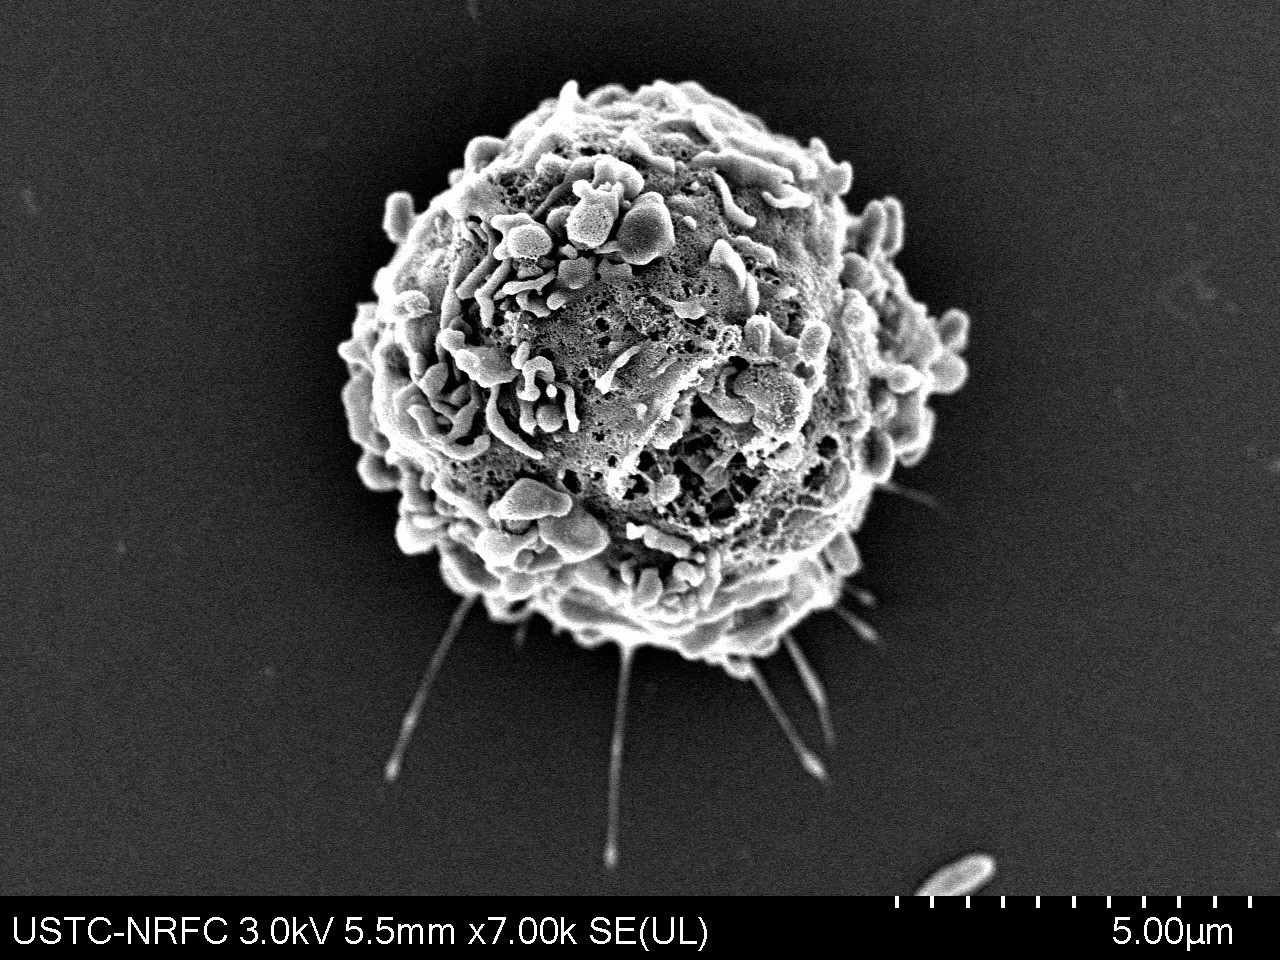

T cells migrating to the lower chamber in the Transwell experiment shown by scanning electron microscopy. -by Quanyin Gu

We systematically investigate the in vivo behavior and fate of drug delivery systems using advanced imaging and analytical tools, including intravital fluorescence microscopy, transmission electron microscopy, and synchrotron radiation-based imaging. Our studies focus on how delivery systems interact with physiological and immune barriers, such as the mononuclear phagocyte system (especially in the liver and spleen), vascular endothelium, and immune cell subsets. We analyze circulation kinetics, biodistribution profiles, cellular uptake mechanisms, and clearance pathways to elucidate the principles that govern delivery efficiency and target-site accumulation. These mechanistic insights guide the rational optimization of carrier design to improve therapeutic precision and minimize systemic toxicity.